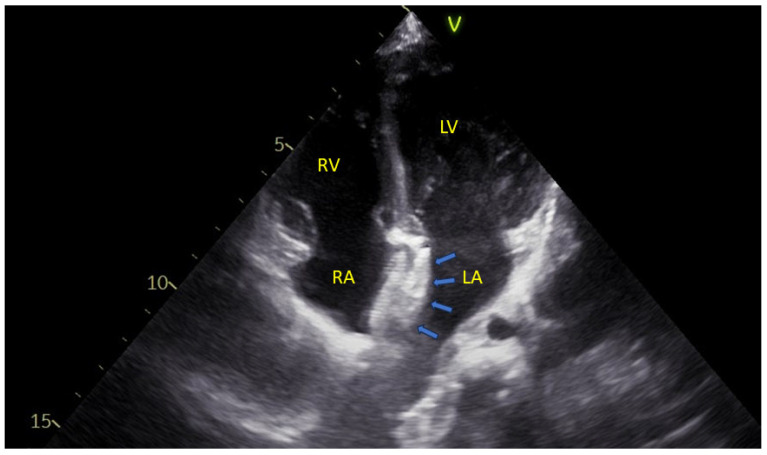

心脏和心血管系统的发育过程是人类发育的基础,受到遗传因素的高度调节。这个过程需要高度规范,以防止畸形。然而,一些心脏缺陷是可以识别的,特别是用现代成像方法。房间隔缺损(asd)尤为常见。了解ASD形成的机制是开发新的治疗策略的基础。在本文中,我们探讨心脏发育和胚胎学,重点关注房间隔缺损及其临床意义。

The development process of the heart and cardiovascular system is fundamental in human development and highly regulated by genetic factors. This process needs to be highly regulated to prevent malformations. Nevertheless, some heart defects may be identified, especially with modern imaging methodology. Atrial septal defects (ASDs) are particularly common. Understanding the mechanisms involved in ASD formation is fundamental for developing new treatment strategies. In this article, we explore cardiac development and embryology, with a focus on atrial septal defects and their clinical implications.